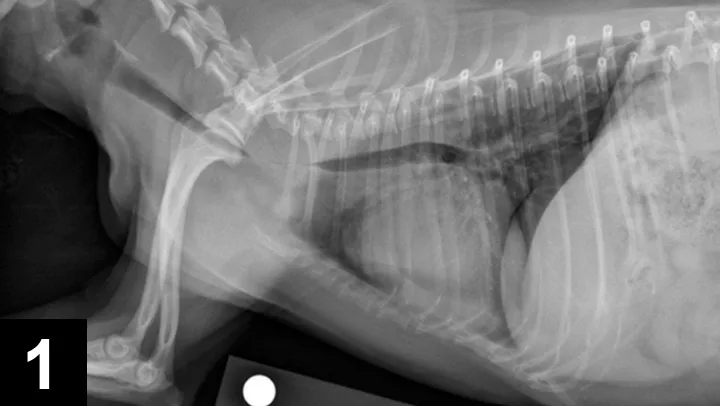

Patients are recovered in an oxygen cage and monitored for signs of respiratory distress. They are sent home on a tapering dose of corticosteroids, 2 weeks of antibiotics, and client instructions to administer sedatives and antitussives as needed. In one study of 18 dogs, the mortality rate was 11.1% within 60 days after stent placement; however, long-term improvement was observed in the remaining dogs.22 Stress, excitement, and exercise need to be limited for 4 weeks. Patients should be reevaluated (ie, examination, survey radiography) at 1, 3, and 6 months procedure. Because the stent initially irritates the airway, coughing is expected but must be controlled to prevent stent fracture (4A, 4B) or granulation tissue formation (4C). Other potentially life-threatening complications include stent migration, tracheal rupture, and collapse of mainstem bronchi or nonstented regions of the trachea. Rare complications include rectal prolapse and perineal hernia.23 Most clients note immediate improvement in quality of life and, despite the progressive nature of the condition, are satisfied with the procedure.

FIGURE 4A

Lateral radiograph of a fractured stent.